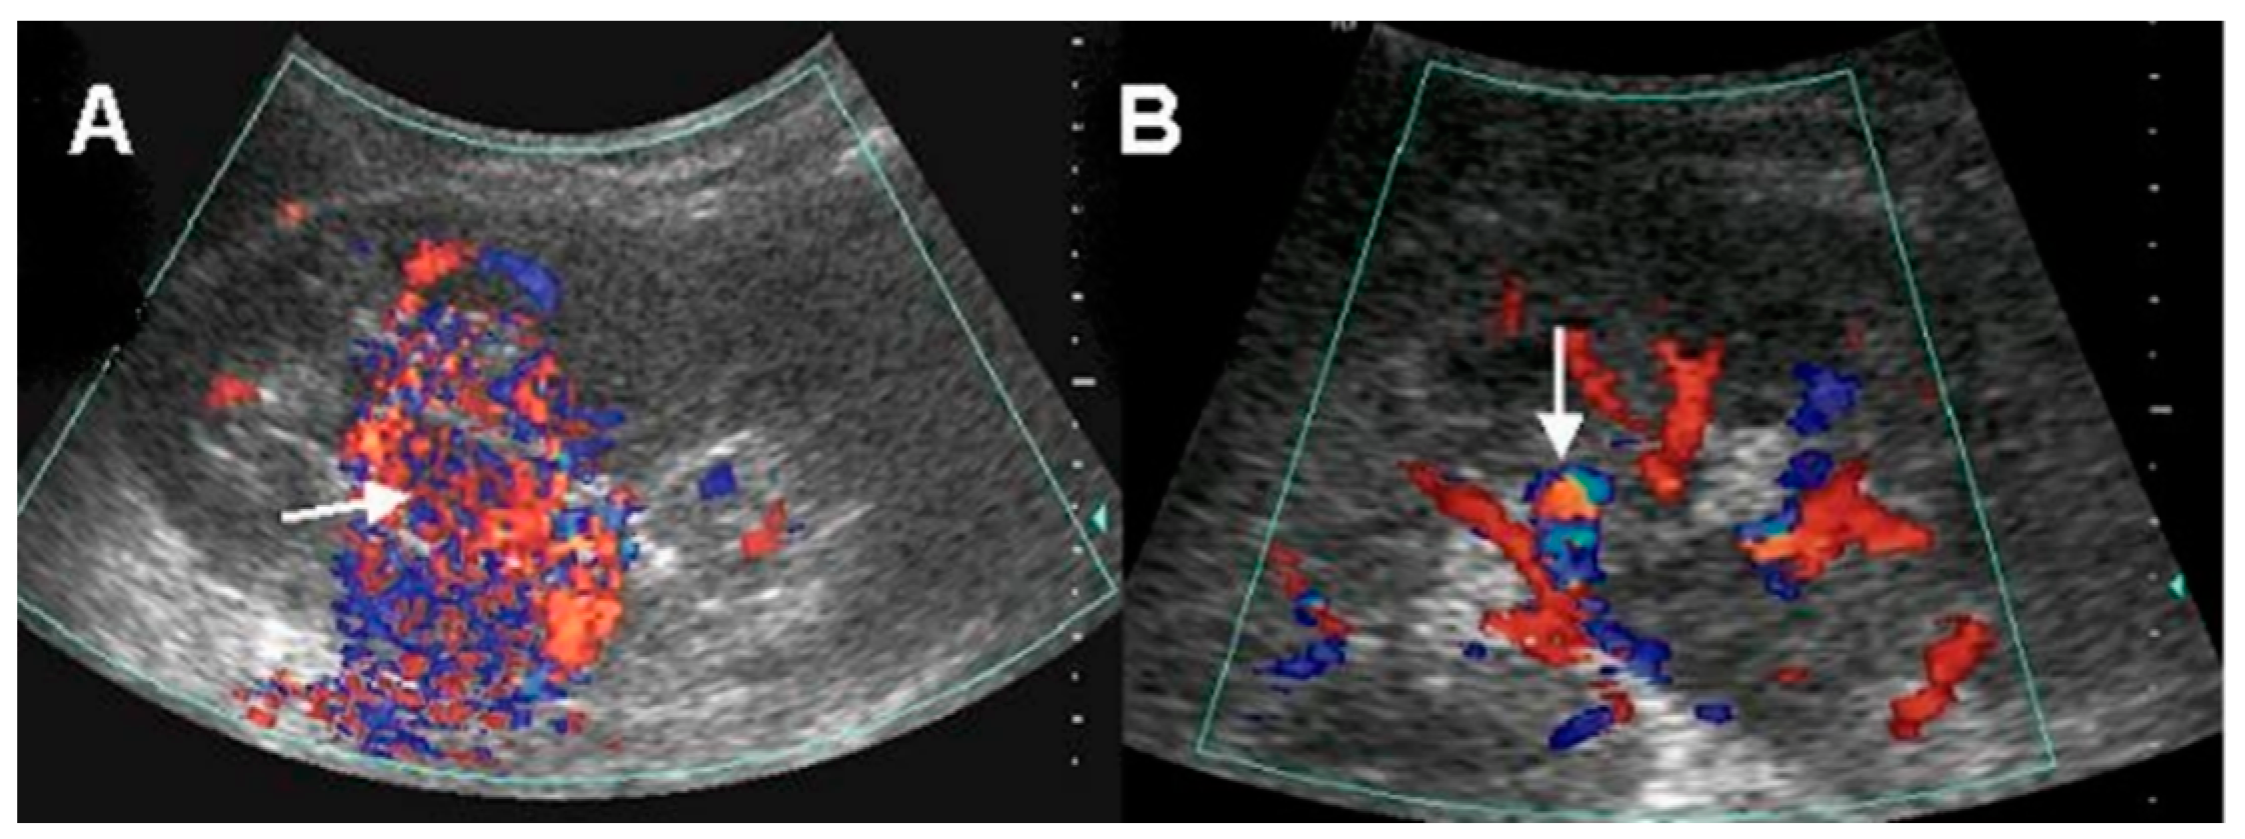

Six (46.2%) patients underwent renal duplex color Doppler US. All of these patients showed a high velocity of blood flow in the renal parenchyma and were correctly diagnosed as AVM. Of them, two (33.3%) patients showed vascular mass-like lesions, and four (66.7%) patients showed a vascular turbulence lesion. (Figure 1).

The duplex color Doppler US in AVM demonstrates multidirectional, turbulent, and increased flow velocity, a mosaic pattern, and perivascular soft tissue color speckling [1,10]. Spectral analysis showed increased velocity and decreased resistance [1,11]. High-velocity blood flow with a diastolic component in the feeding artery and arterial pulsations in the draining vein is characteristic of arteriovenous shunting. Nagamura et al. revealed that color Doppler US in AVM clearly showed an area rich in blood flow with innumerable posterior color spots [12]. Several studies have suggested that duplex color Doppler US is useful in assessment of renal AVM including small cirsoid type and for the differential diagnosis of other mimicking disease entities [10,11,12,13]. Takebayashi et al. assessed color Doppler US in six patients with AVMs. In their study, AVMs were detected with focal areas of flow and as a mixing of lighter colors. They suggested that color Doppler US can be used for diagnosing and monitoring AVMs and could eliminate a considerable number of angiograms [10]. Donmez et al. suggested that duplex color Doppler US provides more information than gray-scale US for the diagnosis of renal AVM with cystic lesions showing the vascularization of the septa or the solid component of the cystic lesion [13]. Using duplex color Doppler US, small renal AVMs that are not visible by conventional US can be detected. We confirmed those findings in this study. In our results, patients who underwent renal duplex color Doppler US were all correctly diagnosed as AVM. Despite its invasiveness, arteriography is the gold standard for evaluating renal AVM. Taken together, we consider duplex color Doppler US as useful non-invasive diagnostic method for renal AVM, and it would be recommended in patients with no apparent cause of hematuria on conventional US or CT.

Figure 1. Doppler ultrasonographic findings: (A) conglomerated vascular structure (arrow) with blood-flow-rich area, (B) vascular turbulence (arrow).